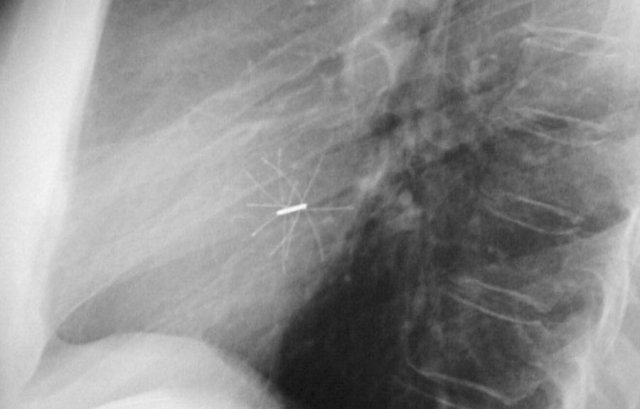

Subtle lead fracture in malfunctioning pacemaker.

Extremely subtle fracture line (arrow).